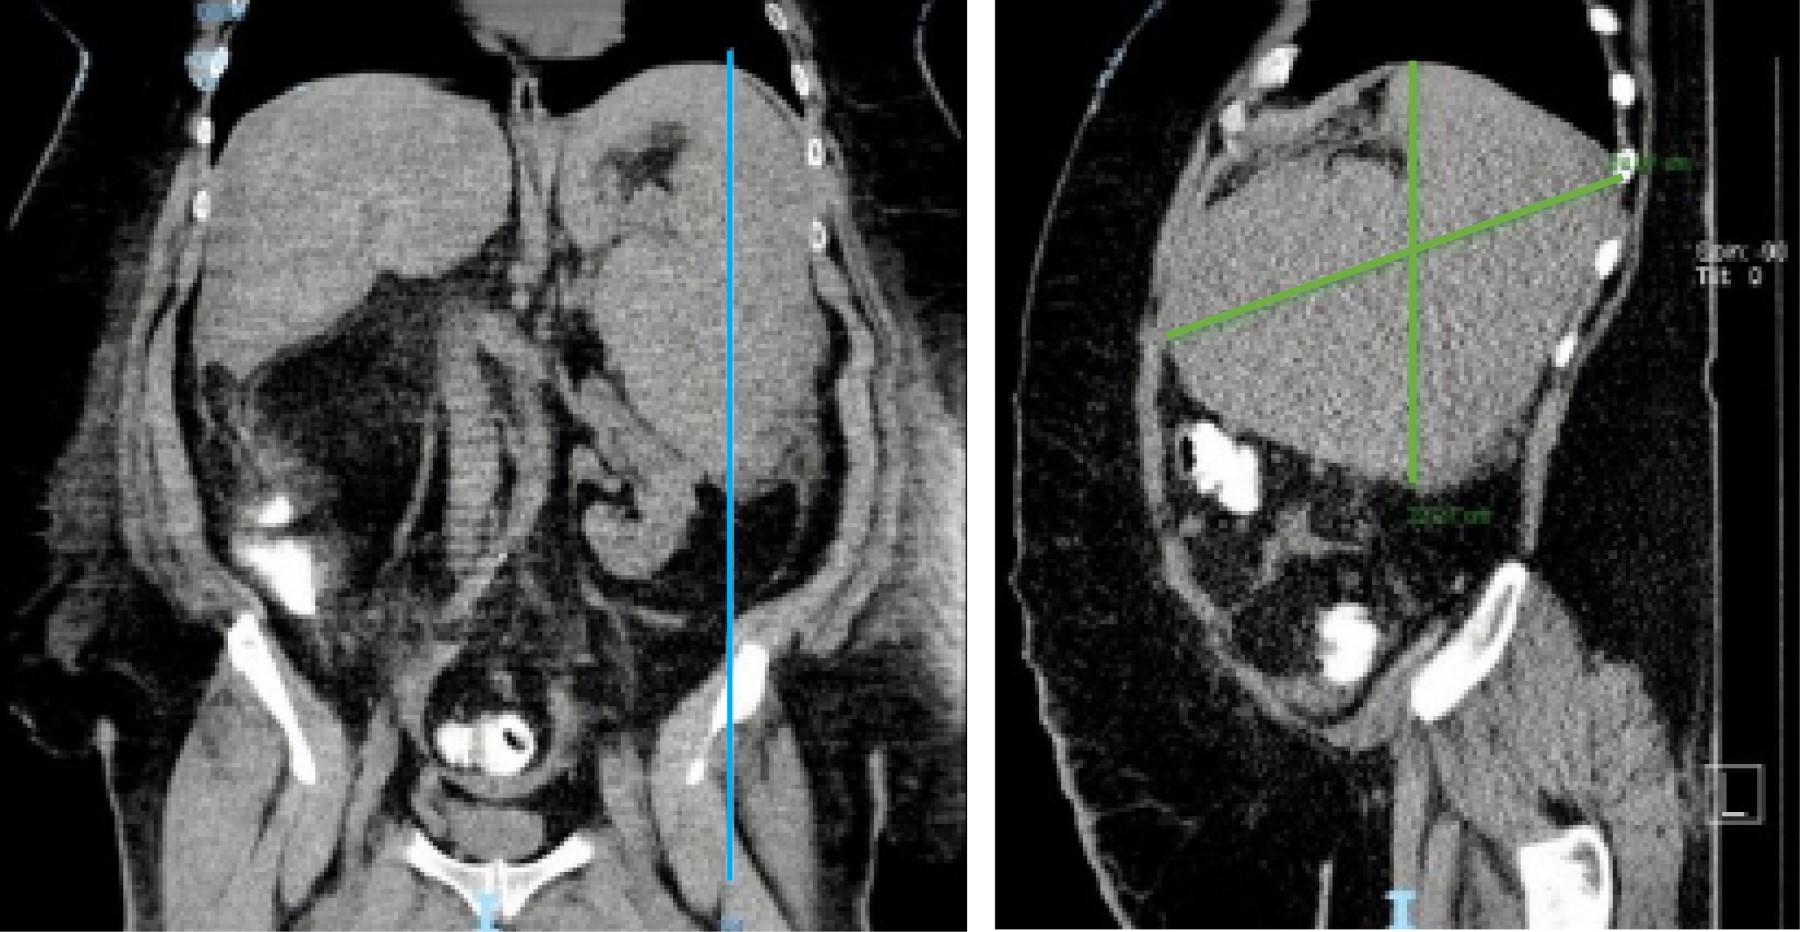

Durante sus primeras horas de estancia intrahospitalaria presentó odinofagia, faringe hiperémica y tos seca, con reporte (+) para virus de Epstein-Barr (VEB). Se solicitó tomografía axial computarizada (TAC) simple de abdomen (Figura 1) reportando derrame pleural bilateral de predominio derecho, esplenomegalia (diámetro máximo de hasta 24 cm), esteatosis hepática con bordes nodulares en su región inferior, presencia de proceso inflamatorio en grasa mesentérica a nivel de mesogastrio con líquido libre en correderas parietocólicas, y en ambas fosas iliacas.

Al introducir el video-laparoscopio se encontró hemoperitoneo de tres litros aproximadamente, esplenomegalia y ruptura de la cápsula, aspecto moteado y sangrado activo (Figura 2); el hígado se observó con apariencia cirrótica y datos de hipertensión portal con sistema venoso colateral umbilical. Ante los hallazgos y la obesidad del paciente, por el espacio reducido, se hizo incisión de 9 cm en flanco izquierdo para retractor mediano (5-9 cm) para continuar procedimiento mano asistida con levantamiento de bazo y mejor control vascular. Además de bisturí armónico (Figura 3), se usó endograpadora vascular de 45 mm para los vasos esplénicos y vasos cortos, debido a su grosor. Se dejaron hemostáticos en lecho esplénico, se visualizó sangrado hepático en capa, y a causa de las condiciones hemodinámicas y de coagulopatía de consumo, se decidió empaquetamiento hepático con compresas introducidas a través de puerto mano asistida, se colocaron dos superiores al hígado y una inferior. Se colocó drenaje cerrado subfrénico izquierdo, se finalizó evento quirúrgico, trasladando al paciente a la unidad de cuidados intensivos (UCI), la pieza midió 24 cm (Figura 4). Durante las primeras horas posquirúrgicas disminuyó gasto hemático por drenaje y mejoró estabilidad hemodinámica.

Figura 1

Figura 4